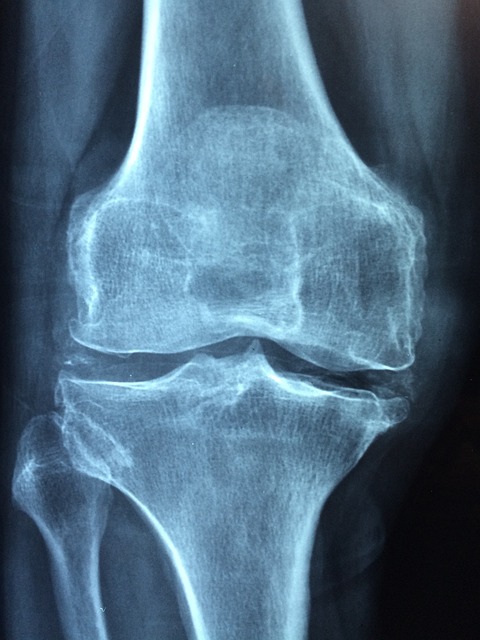

- 뼈의 주요 성분인 마그네슘은 뼈의 강도를 유지하고 골다공증 예방에 기여합니다.

1) 뼈 강화

마그네슘은 칼슘과 함께 뼈의 주요 성분입니다.

마그네슘은 뼈의 형성과 유지에 필수적인 역할을 하며

골밀도를 높여 골다공증을 예방하는 데 도움이 됩니다.

특히 칼슘과 함께 섭취하면 시너지 효과를 발휘하여 뼈 건강을 더욱 강화할 수 있습니다.